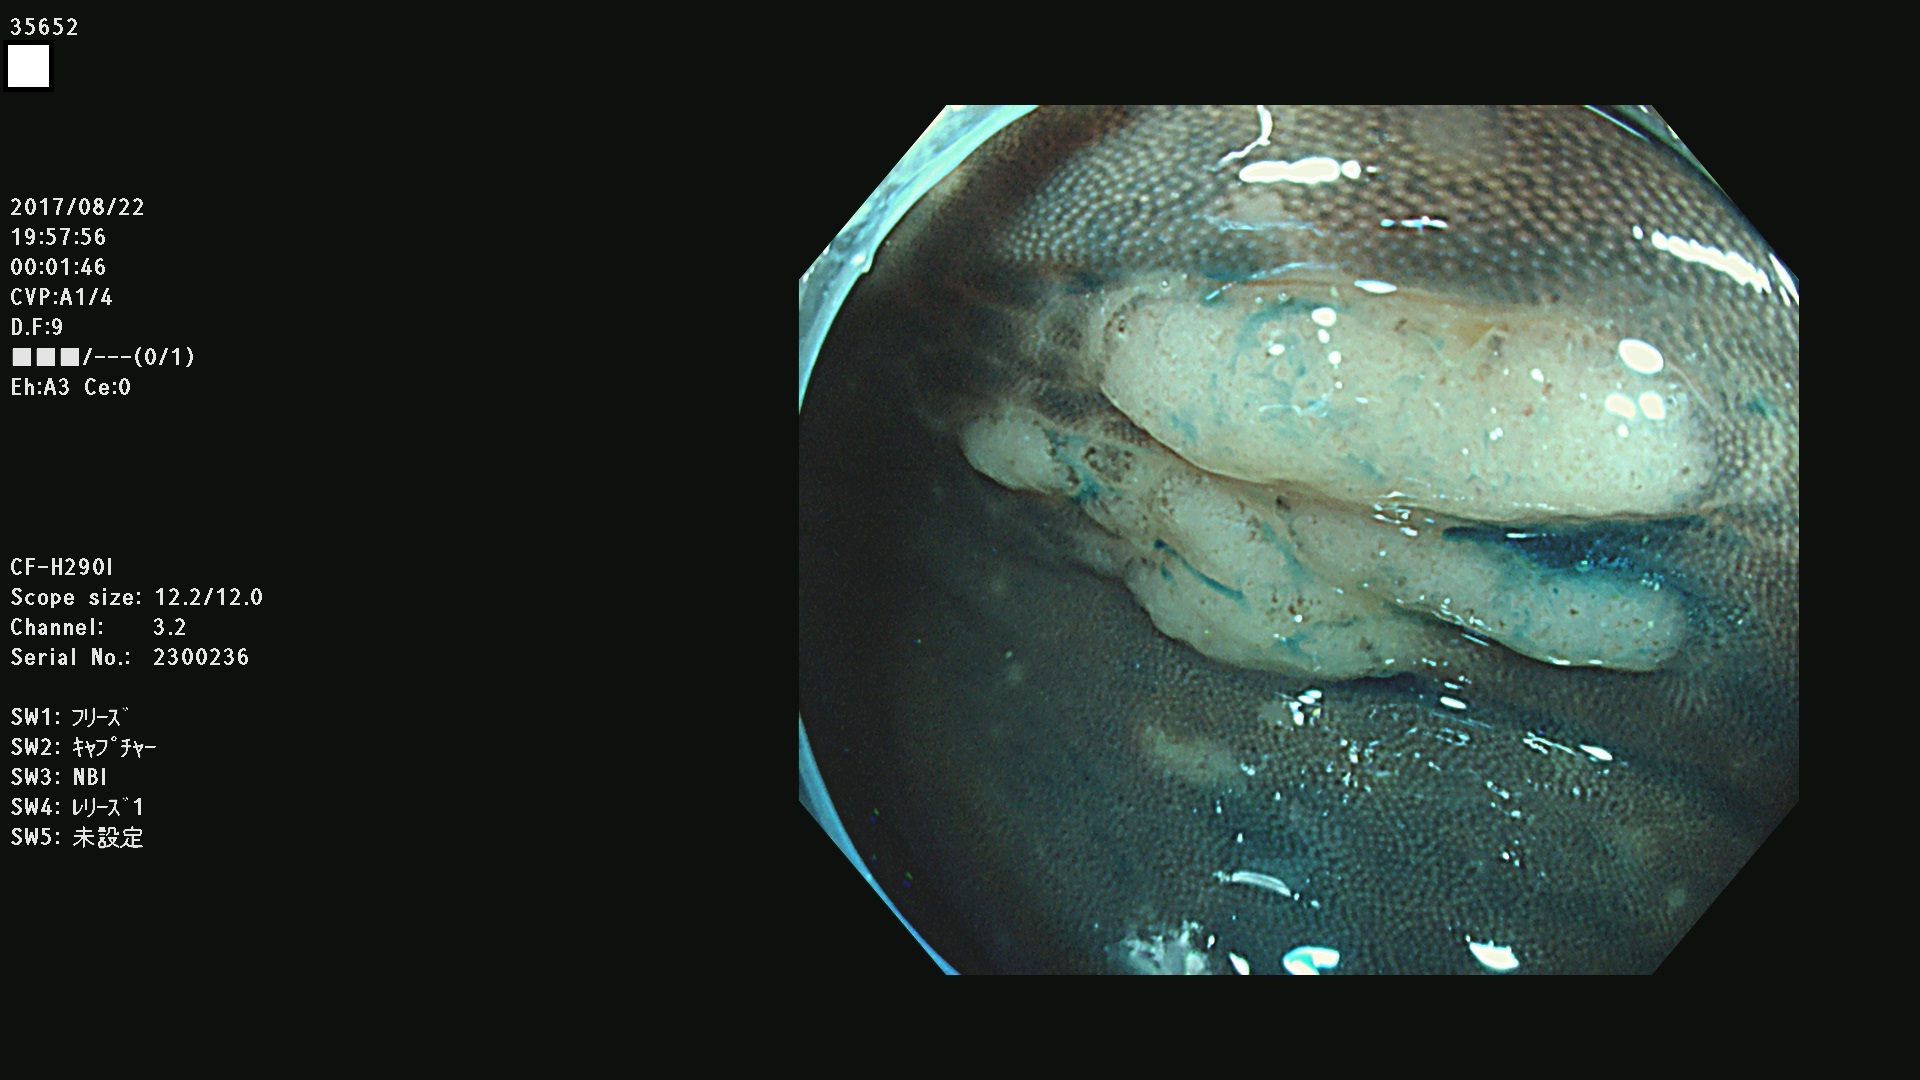

発見困難で危険性の高い平坦型病変(上記100名より抽出)

35600 35603 35604 35609 35612 35613 35614 35619(SSA/Pのみ) 35624 35625 35626 35627 35629 35630 35631 35633 35634 35635 35636 35638 35641 35642 35643 35644 35645 35646(SSA/Pのみ) 35648 35651(SSA/Pのみ) 35652 35653 35655 35656(SSA/Pのみ) 35659 35660 35664 35665 35667 35668 35669 35670 35671 35675 35678 35679 35680 35682 35684 35689(SSA/Pのみ) 35695 35696 35699